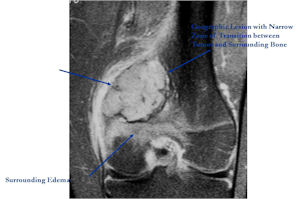

MRI:

- Also useful in determining extent

- There is often extensive edema around the tumor in the surrounding bone and soft tissues that can lead to a misdiagnosis of a malignant tumor.